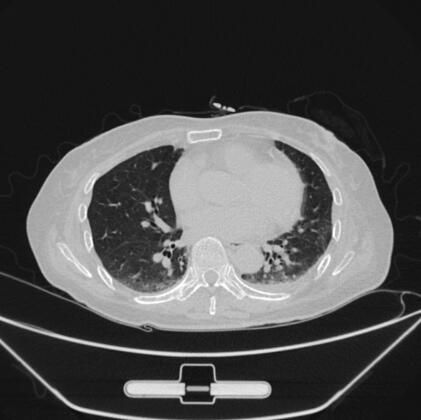

26日8时30分,复查B型脑钠肽2755pg/ml、心肌钙蛋白-I 8.92μg/L,给予静脉泵入新活素(冻干重组人脑利钠肽),同时限制液体输入,加强利尿,使出入量呈负平衡,在500ml左右,并控制血压,使收缩压<130mmHg,减轻心脏前后负荷,经采取上述治疗措施后,动态监测心肌钙蛋白-I、B型脑钠肽,指标逐日降低(图3、图4),症状明显改善。入院时应用美罗培南抗感染治疗,2天后出现发热,体温最高达38.2℃,WBC最高达39.52×109/L,N 95%,CRP最高达257mg/L,改用莫西沙星注射液400mg,每日1次,治疗第2天未再发热,WBC、CRP逐日下降至正常(图5),胸部CT示双肺炎症明显吸收(图6、图7),感染得到有效控制。

图6 治疗后胸部CT示双肺炎症明显吸收(肺窗)